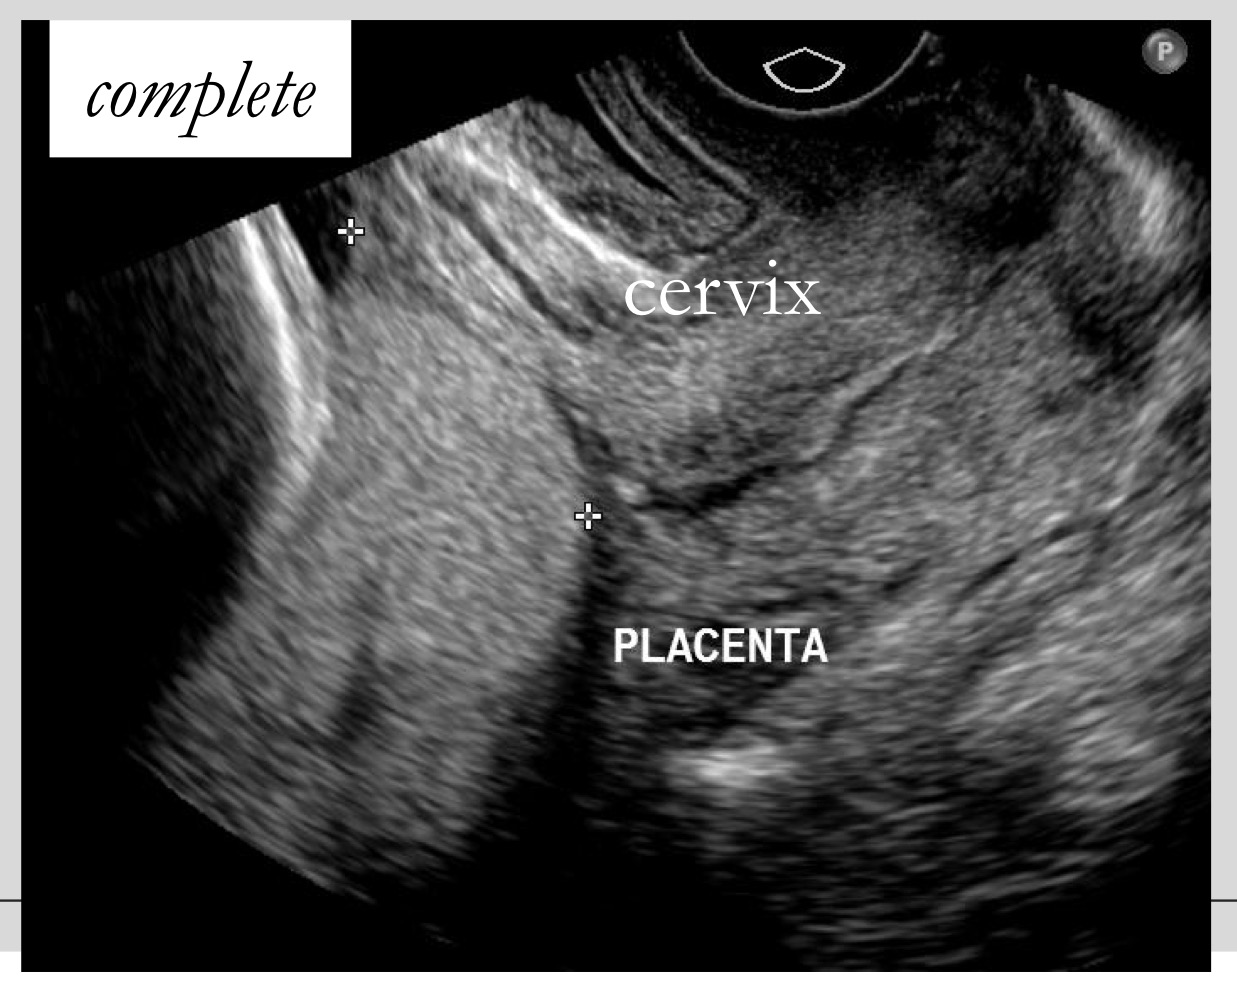

Definition of complete placenta previa

Placenta completely covers the internal os

What is the main symptom of complete placenta previa

Bright red painless vaginal bleeding in second half of pregnancy

What type of delivery is usually required for complete placenta previa

Cesarean section

What is seen in complete previa on imaging

Placenta covering the cervical canal/internal os

What imaging method is best for evaluating placenta previa

Transvaginal ultrasound